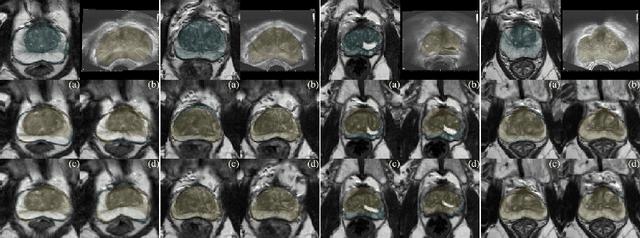

Abstract:Various convolutional neural network (CNN) based concepts have been introduced for the prostate's automatic segmentation and its coarse subdivision into transition zone (TZ) and peripheral zone (PZ). However, when targeting a fine-grained segmentation of TZ, PZ, distal prostatic urethra (DPU) and the anterior fibromuscular stroma (AFS), the task becomes more challenging and has not yet been solved at the level of human performance. One reason might be the insufficient amount of labeled data for supervised training. Therefore, we propose to apply a semi-supervised learning (SSL) technique named uncertainty-aware temporal self-learning (UATS) to overcome the expensive and time-consuming manual ground truth labeling. We combine the SSL techniques temporal ensembling and uncertainty-guided self-learning to benefit from unlabeled images, which are often readily available. Our method significantly outperforms the supervised baseline and obtained a Dice coefficient (DC) of up to 78.9% , 87.3%, 75.3%, 50.6% for TZ, PZ, DPU and AFS, respectively. The obtained results are in the range of human inter-rater performance for all structures. Moreover, we investigate the method's robustness against noise and demonstrate the generalization capability for varying ratios of labeled data and on other challenging tasks, namely the hippocampus and skin lesion segmentation. UATS achieved superiority segmentation quality compared to the supervised baseline, particularly for minimal amounts of labeled data.